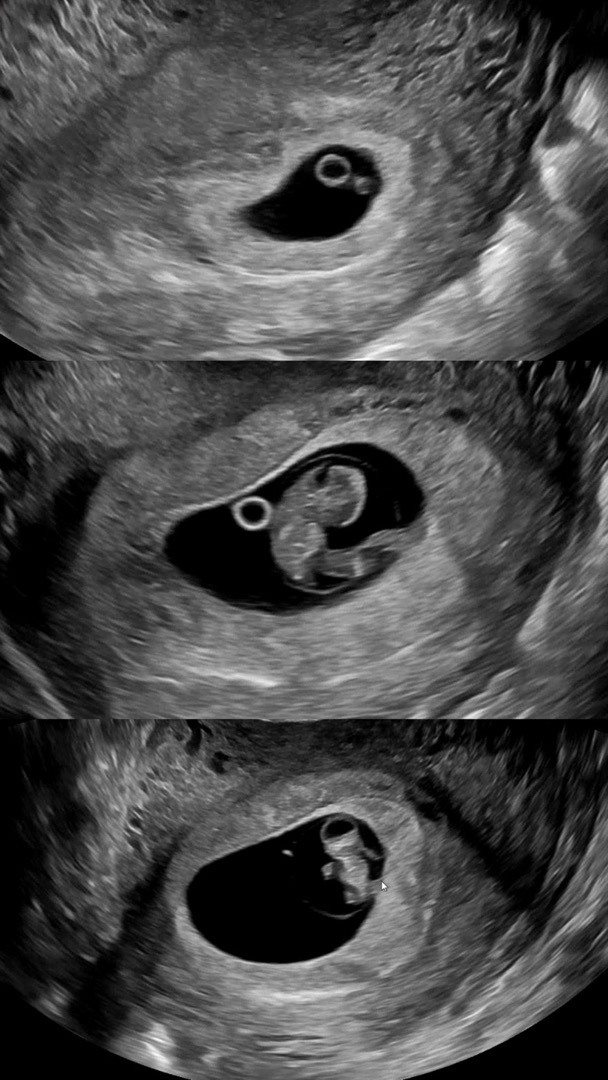

8주 2일! 6주3일과 비교해서 많이컸어요!

8주2일! 우렁찬 심장소리랑, 귀여운 아가 옆모습과 젤리곰 보고왔어요!! 탯줄 연결된것도 보고 분명 6주에는 난황옆에 딸린 작은 보석이었는데 쑥쑥 자라주니 너무너무 기쁘네요💗 너무 예뻐서 남겨봐요🤭💕 입덧도 그렇고 내몸같지않아서 자주 속상하기도했는데, 정말 아기만 주는 기쁨이 따로 있네요!! 12주차 기형아검사때보자는데 ..! 한달..! 잘기다려보려구요💗💗 6주3일 심소 125bpm 아가 0.5cm 8주2일 심소 183bpm 아가 1.8cm 모든 마미들 축복해요💗💗